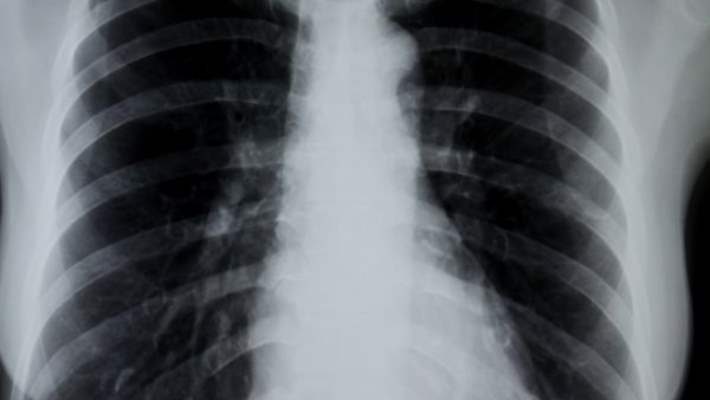

Bronşitin Teşhisi